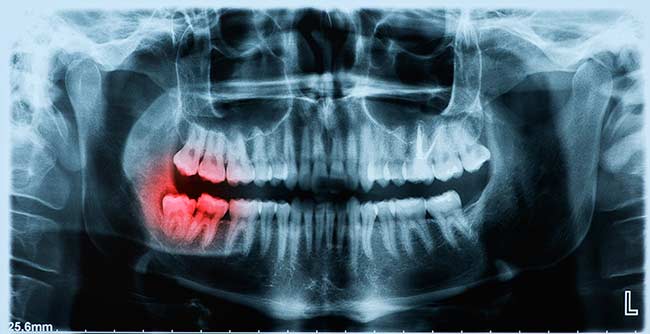

wisdom-teeth-removal-xray

Wisdom teeth are also known as third molars and usually appear when we are between 17-25 years of old. Wisdom teeth don’t always erupt as they should, and if you have only seen partial impact or eruption of your teeth chances are you’ll be feeling some or even extreme discomfort. We can assist you if you do need to remove wisdom teeth that are causing you pain.Don’t live with pain and discomfort any longer. Schedule an exam today!

Before surgery begins, you can take part in a consultation to ensure the right treatment is being offered. You will be given a local anaesthetic on the day of the removal to numb the area and may also need a general anaesthetic if multiple teeth are being extracted. Your surgeon will open up gum tissue near the tooth and remove any hone over it before extracting the tooth. They may need to cut the tooth into small pieces to extract it. Wisdom tooth removal is likely to be easier if the tooth has fully erupted, but the process may be more complex if the only partial eruption has occurred. In any case, wisdom tooth removal can help you avoid tooth decay, lift you out of pain and give you a straighter bite.